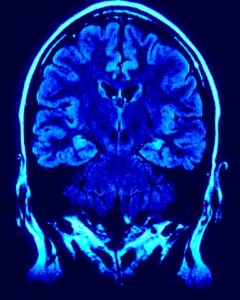

Alabama Brain Injuries Have Life-Altering Impact on Adults, Children

But our Birmingham brain injury lawyers know that was before a training run crash in Park City, Utah on Dec. 31, 2009. He suffered massive trauma to his body, and his brain. He lapsed into a coma. Some thought he might die.

Of those visits, about 12 percent were for concussions. What that means is that a child suffers a concussion – a type of head injury – every three minutes as a result of sports injuries. Doctors reported that many of these injuries are being reported in younger and younger athletes. In fact, nearly half of those occurred in children between the ages of 12 and 15.

Even more disturbing is that severe brain swelling – the kind that can have long-lasting consequences or even be deadly – is more common in youth with traumatic brain injury than adults.

While the damage inflicted by a brain injury can be swift and severe, sometimes the problem is that the long-term effects are only revealed over time. This was part of the reasoning behind the American Academy of Neurology’s updated guidelines for head injuries suffered in athletic competition.